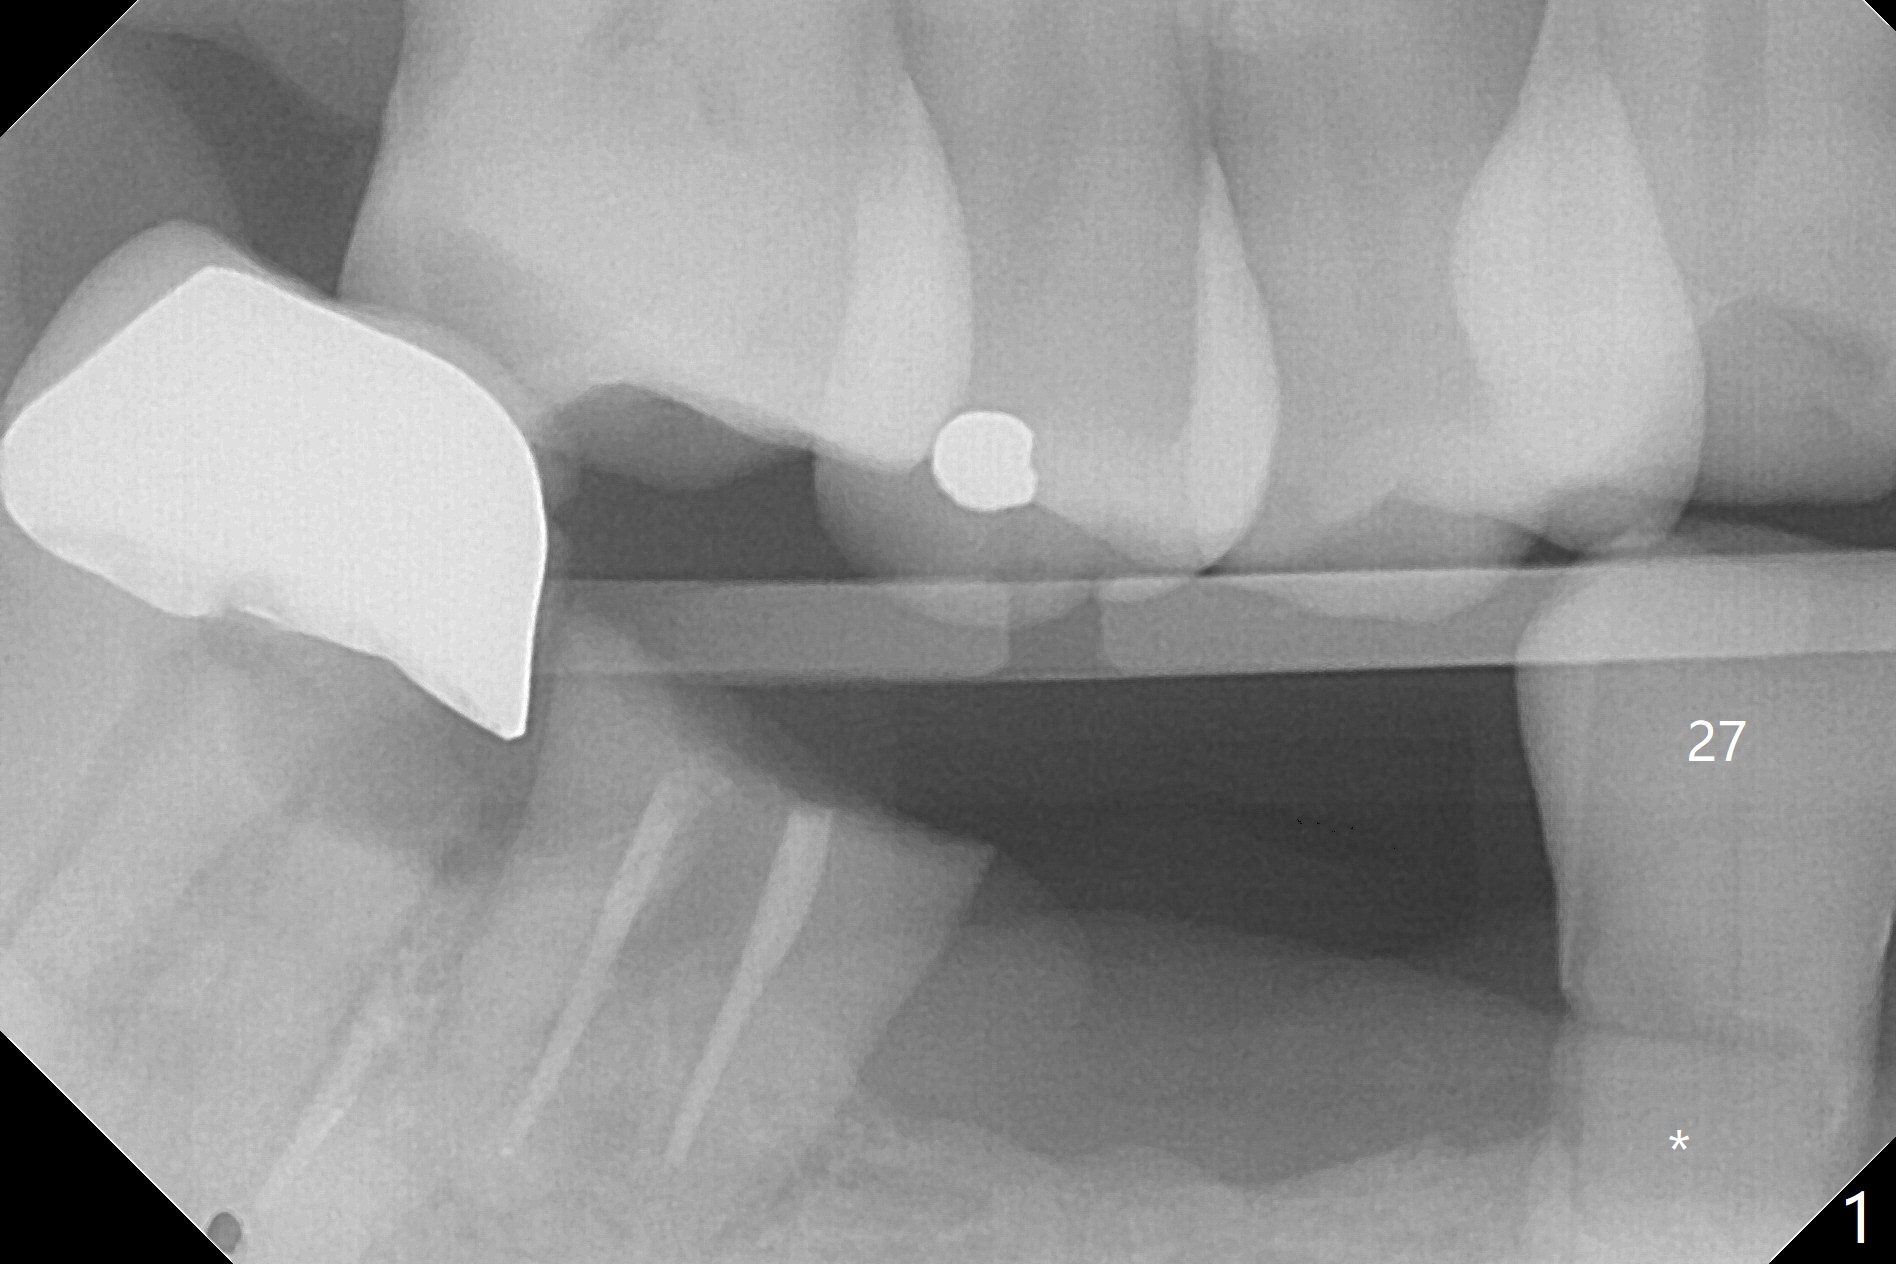

Deep Class V Caries M

A 63-year-old man requests repair of Class V caries at #27 (Fig.1,2 *). With local anesthesia, Diode laser is used for gingivectomy for composite (Fig.3 C).